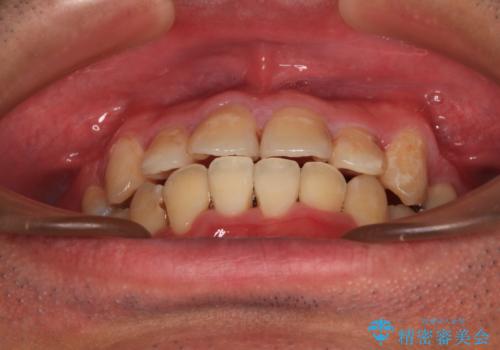

- 上下の八重歯やデコボコを気にして来院された患者様です。

上下ともに八重歯が顕著であったので、上下左右第一小臼歯4本を抜歯し、ワイヤー装置にて矯正治療を行うこととしました。

デコボコが強いことが原因で歯間部に汚れが溜まりやすい状態でしたが、矯正前にできる限り汚れが少なくなるようにブラッシングなどの指導を行い、口腔状態が改善された後にワイヤー装置を装着することとしました。